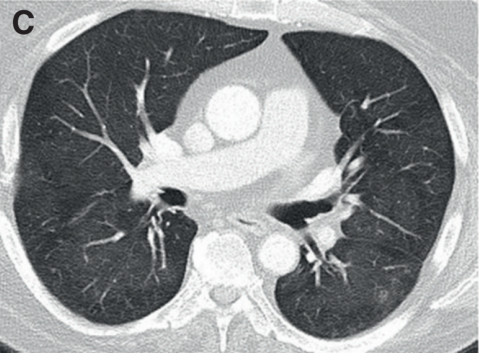

(3)非特异性间质性肺炎(NSIP):是CIP第二常见的报道类型,通常表现为肺下叶GGO和网状结构[17]

图片